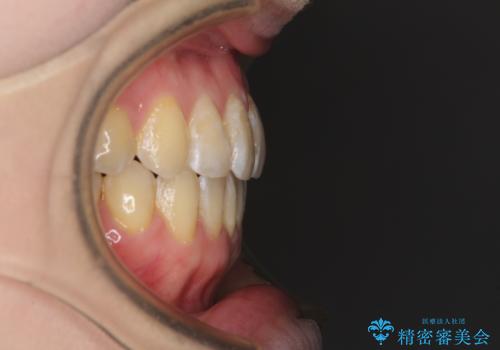

前歯のデコボコを治したい インビザラインによる矯正治療

- 前歯のデコボコを治したいとのことで来院された患者様です。

上下顎ともに歯列全体の後方移動とIPR(歯と歯の間を削る)によってデコボコが解消するように設計し、インビザラインにより治療を行うこととしました。